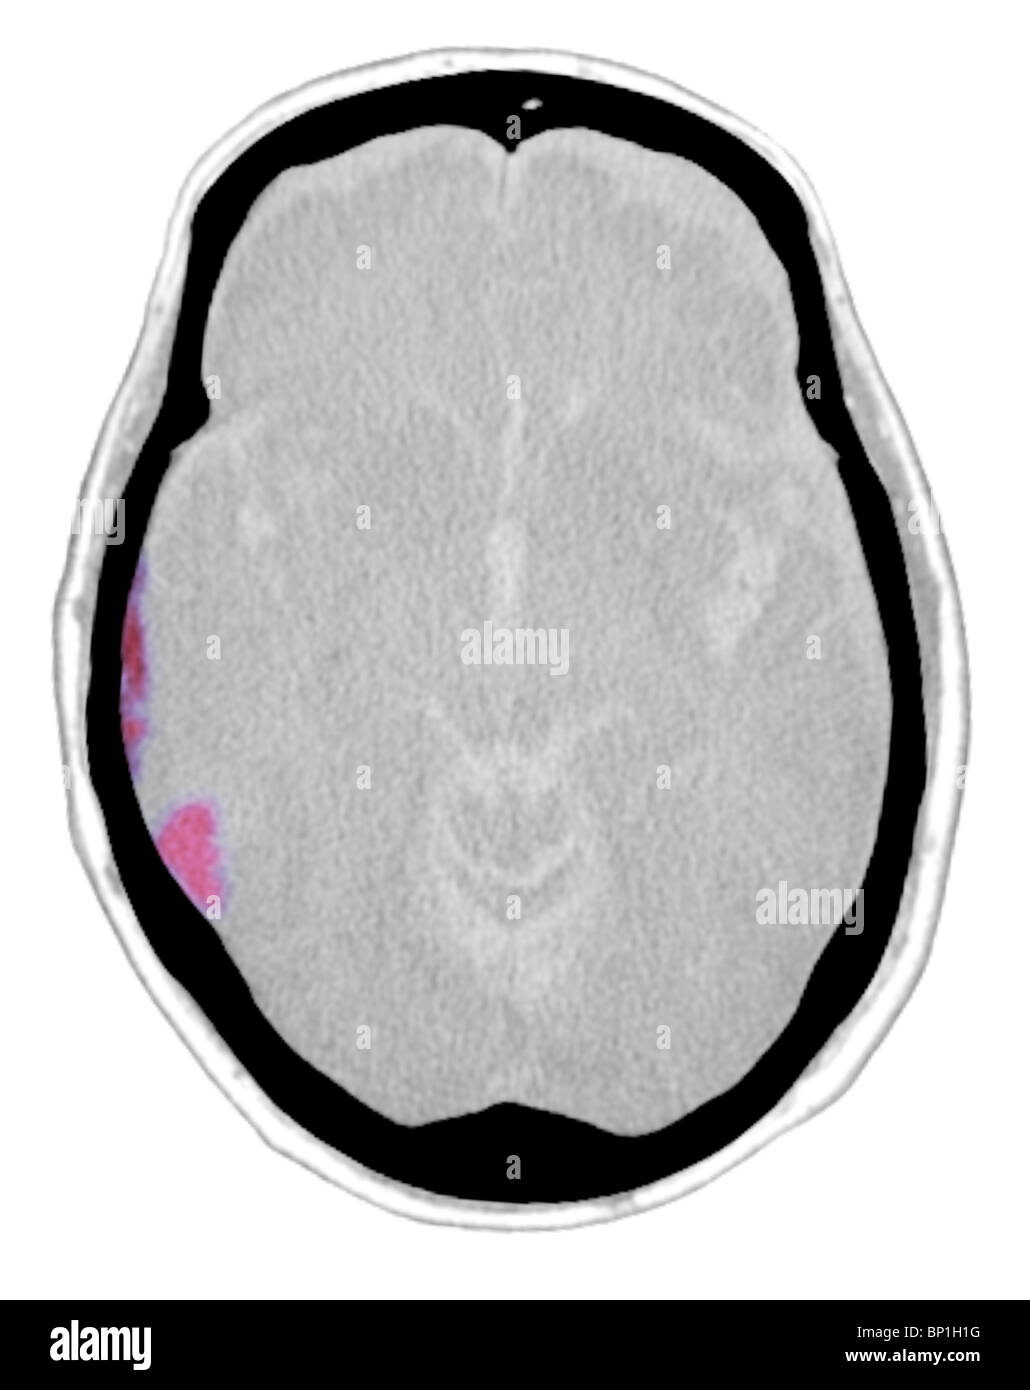

Testa Di Scansione Tc Con L Ematoma Subdurale Atrofia Foto Stock Alamy

Scansione Tc Del Cervello Che Mostra L Ematoma Subdurale Foto Stock Alamy

Scansione Tc Della Testa Che Mostra Un L Ematoma Subdurale Foto Stock Alamy

Scansione Tc Della Testa Con L Ematoma Subdurale Foto Stock Alamy